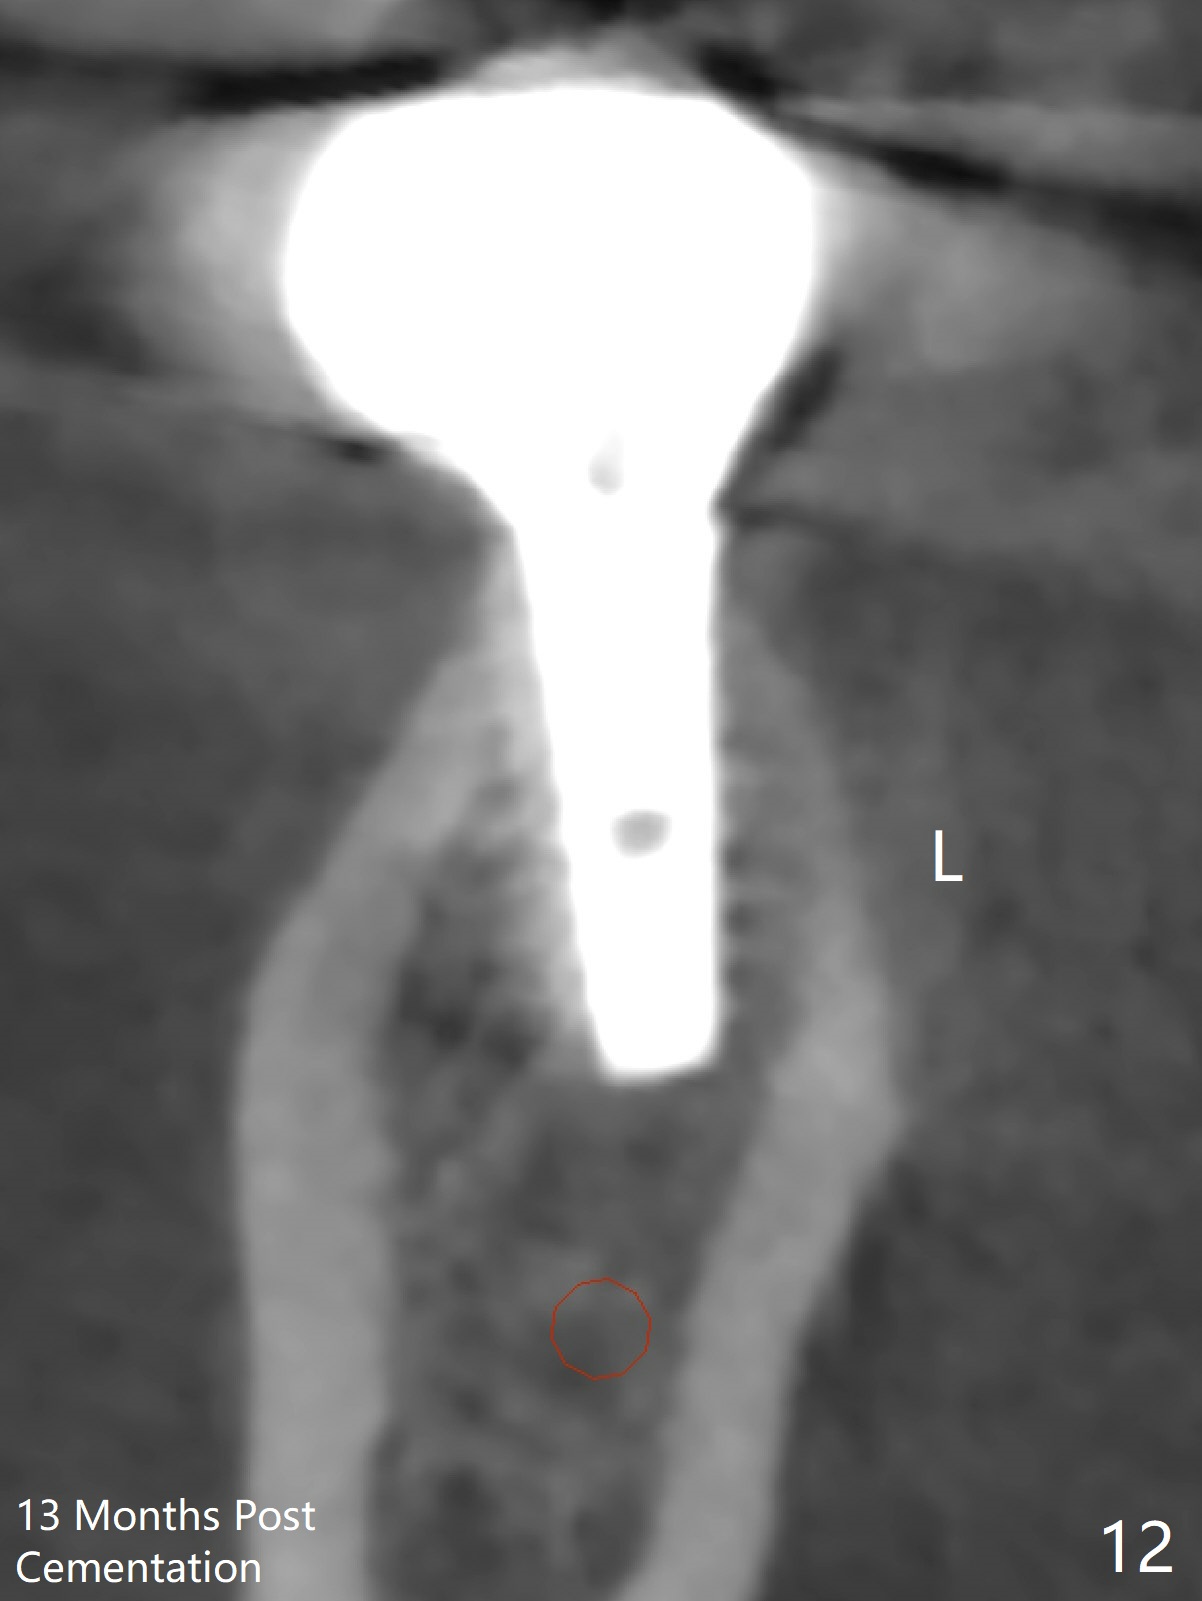

A provisional is fabricated 1 month postop to prevent the tooth #31 from rotation under the tension of the open coil spring, as mentioned above. Acrylic is added distal for #31 distalization nearly 2 months postop. More definitive orthodontic action begins 3 months postop (Fig.7, banding and open coil spring). The edentulous space increases to satisfactory width 3.5 months postop (Fig.8). A normal sized crown is delivered 4 months postop (Fig.9). The patient is pleased with the new tooth (Fig.10 nearly 6 months post cementation). There is no bone loss 13 months post cementation (Fig.11 (pan), 12 (CT coronal section (L: lingual))).